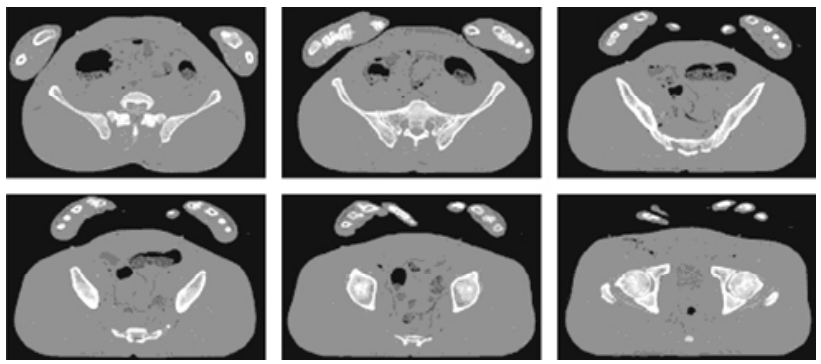

- 아래 그림의 실험에서 사용된 CT 슬라이스 이미지이다. 각각 587 X 341 픽셀이다.